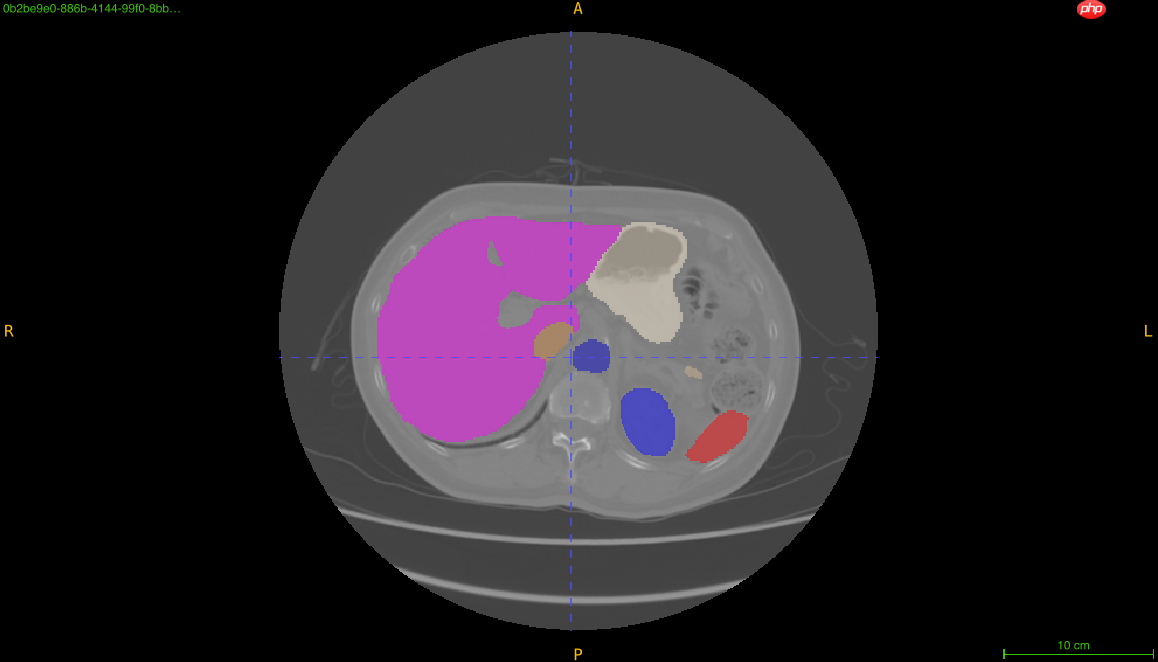

多器官数据集共有11个器官的标注,包括脾脏、右肾、左肾、胆囊、食道、肝、胃、主动脉、下腔静脉、胰腺、膀胱。本数据集共包含160个训练数据,40个测试数据。